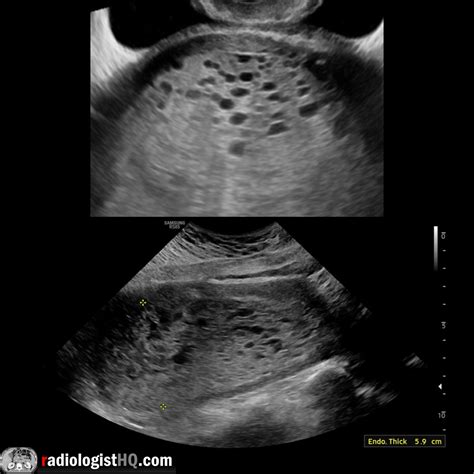

During the scan, a sonographer or radiologist uses high-frequency sound waves to create images of the uterine cavity. In a healthy pregnancy, the ultrasound will show a clear gestational sac with a developing fetus. In contrast, the imaging of a molar pregnancy displays distinct patterns that deviate from normal development.

Radiologists look for specific visual markers to identify this condition. The most classic description of a molar pregnancy ultrasound image is often called the "snowstorm" appearance. This occurs because the abnormal placental tissue creates multiple echo-producing interfaces, making the interior of the uterus look like a blizzard on the screen.

• Absence of Fetal Parts: In a complete mole, there is an absolute lack of fetal tissue.

• Cystic Spaces: Large, fluid-filled cysts are often visible within the mass.